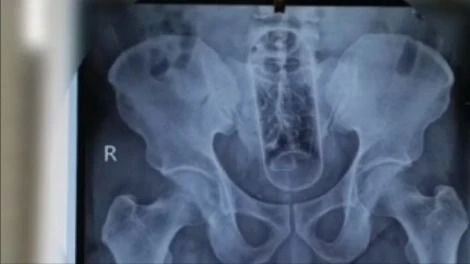

Ảnh chụp chai nhựa dài khoảng 20cm nằm trong hậu môn trực tràng người đàn ông

Kết quả chụp X-quang cho thấy dị vật nằm cách hậu môn khoảng 5 cm nên bệnh nhân được chỉ định phẫu thuật cấp cứu ngay.